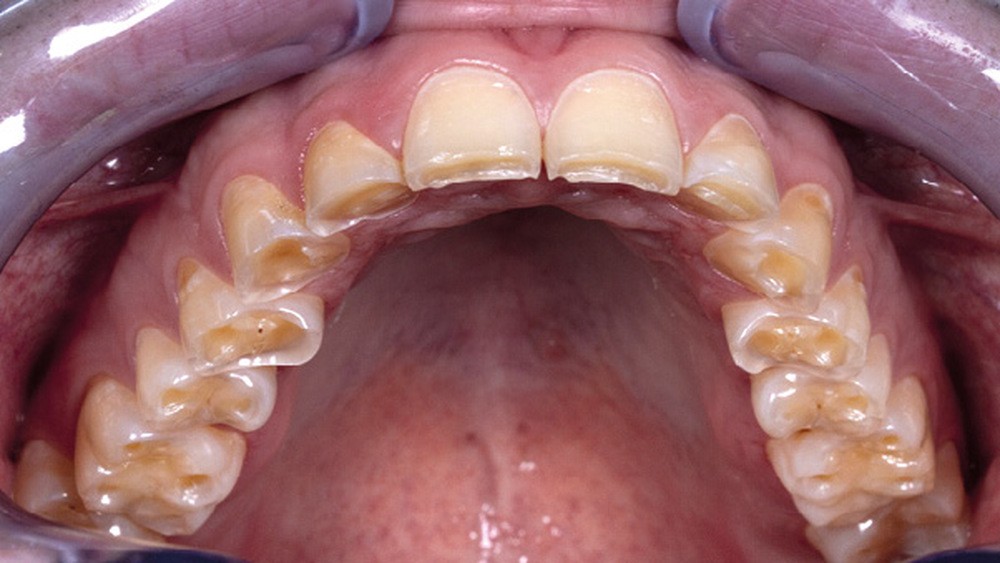

Les indications des veneerlays sont principalement rencontrées dans la prise en charge thérapeutique des lésions d’érosion/usure dans lesquelles la perte des tissus amélaires et dentinaires impacte les faces vestibulaires et occlusales [1]. Les situations cliniques peuvent concerner aussi bien une usure sectorielle (fig. 1a) que globale (fig. 1b).